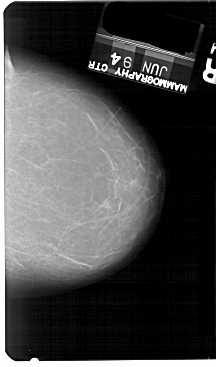

A_1437_1.RIGHT_MLO

RIGHT_MLO LINES 5491 PIXELS_PER_LINE 3721 BITS_PER_PIXEL 12 RESOLUTION 43.5 NON_OVERLAY

FILE: A_1437_1.LEFT_CC.OVERLAY

TOTAL_ABNORMALITIES 1

ABNORMALITY 1

LESION_TYPE MASS SHAPE IRREGULAR MARGINS ILL_DEFINED

ASSESSMENT 3

SUBTLETY 2

PATHOLOGY BENIGN

TOTAL_OUTLINES 1

BOUNDARY